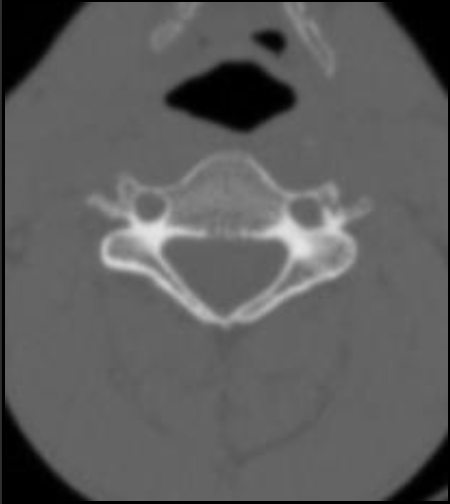

C1

寰椎前结节

C1 anterior tubercle

寰椎后弓及后结节

C1 posterior arch & tubercle

C1 transverse process

寰椎横突